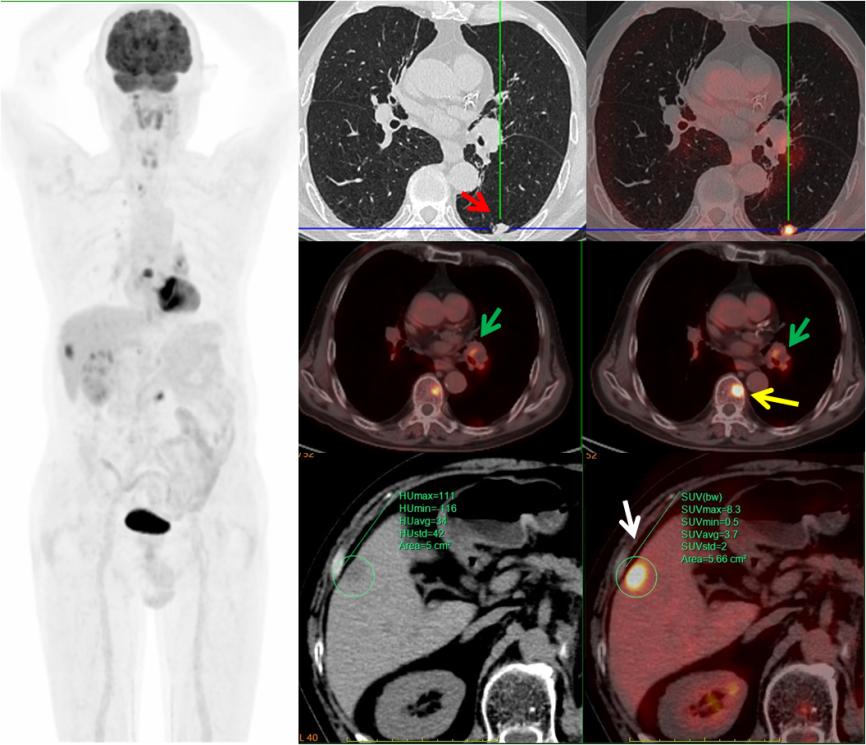

病例3,中年男性,左腎癌術后三個月,PET/CT示左肺下葉(紅箭)、左肺門淋巴結(綠箭)、肝臟(白箭)、多發(fā)椎體(黃箭)高代謝灶,考慮左肺下葉原發(fā)MT可能,病理證實為小細胞神經(jīng)內(nèi)分泌癌。